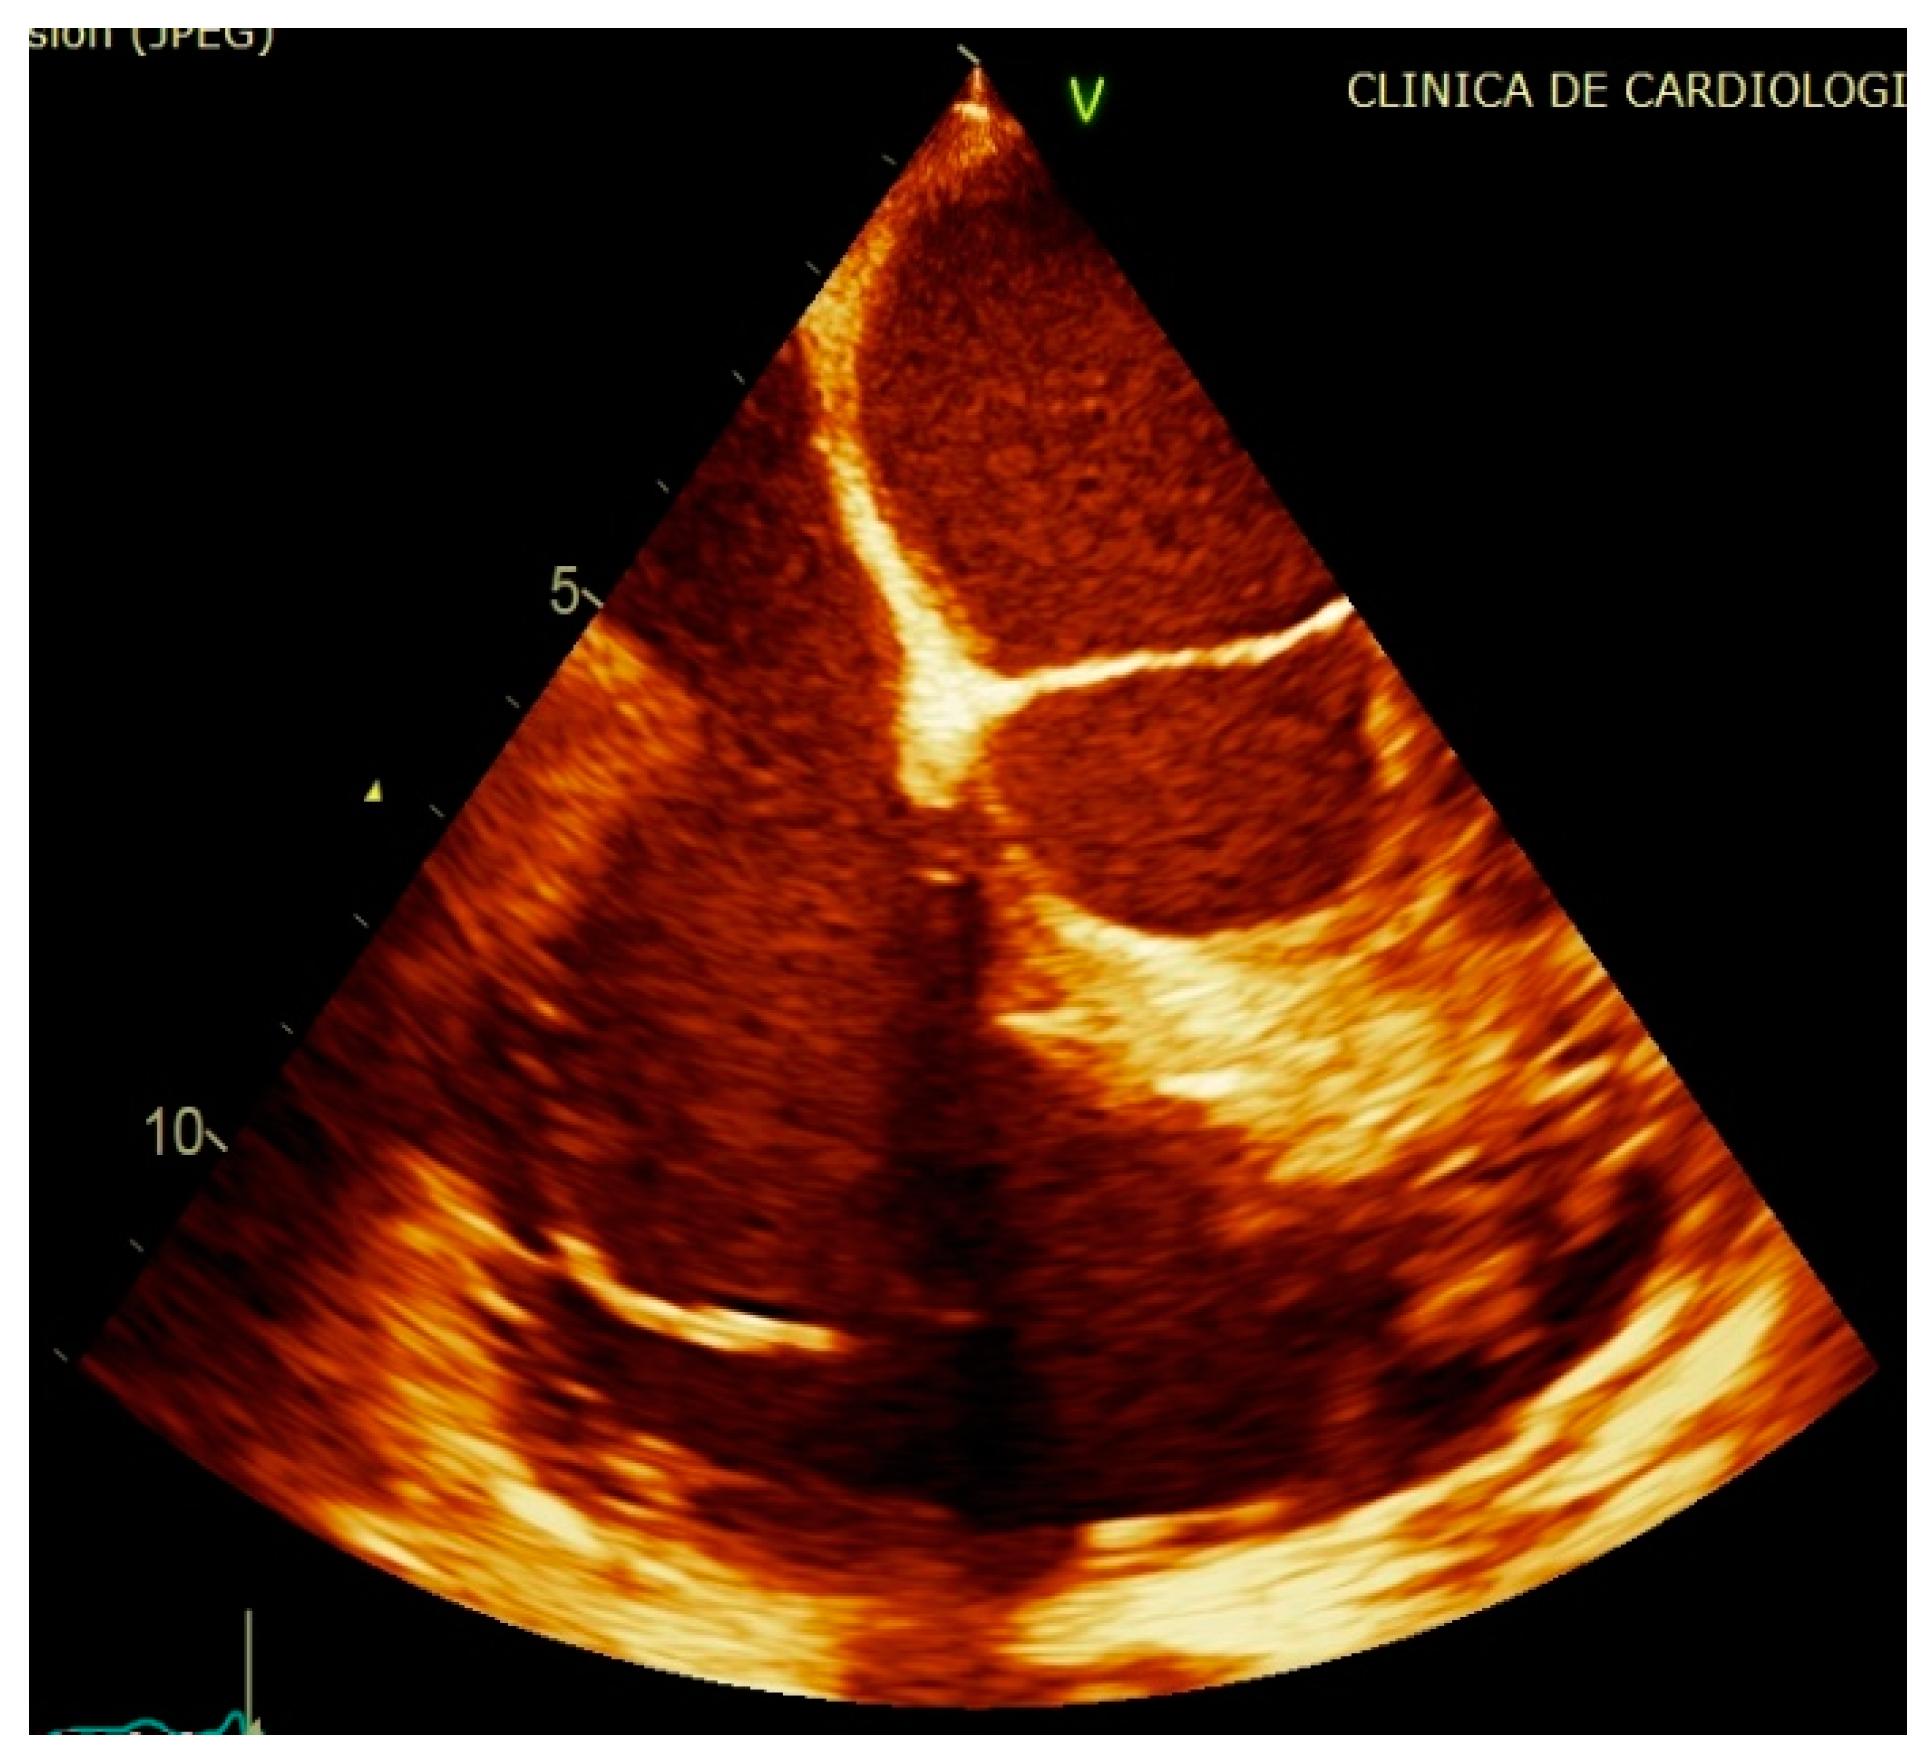

2. Case Report